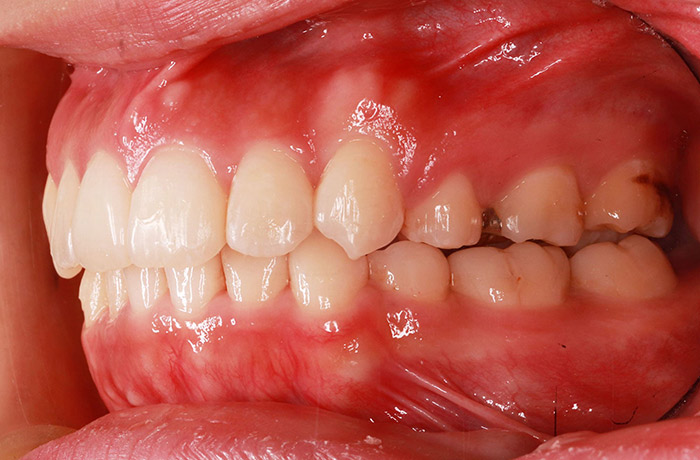

after

年齢 24歳

性別 女性

治療名称 マウスピース型カスタムメイド矯正歯科装置(インビザライン)・コンプリヘンシブパッケージ(フルパッケージ)

総額治療費用 770,000円(税込10%) 金額備考 精密検査料・診断料 33,000円(税込10%)

治療期間 10か月 通院頻度など 1か月ごと

患者の症状 上顎前歯の前突、開咬、下顎前歯部の空隙

治療方法 非抜歯で、マウスピース型カスタムメイド矯正歯科装置による矯正

上顎臼歯の遠心移動とIPR(歯間隣接面を削合)しました。

治療結果 上顎前歯の前突、開咬が改善されました。

その他治療に関する情報 顎間ゴムの使用を24時間指示しました。

リスク/副作用 1日22時間以上、装置の装着と顎間ゴムの使用が必要です。